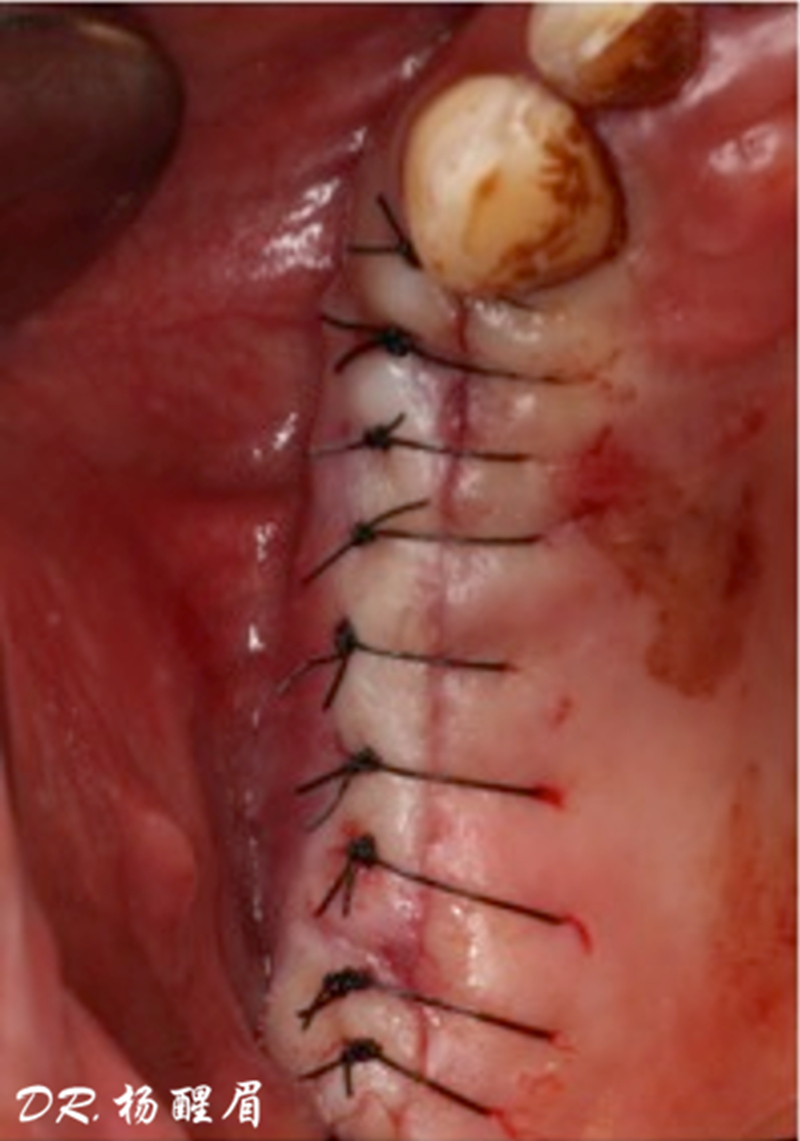

®進行縫合